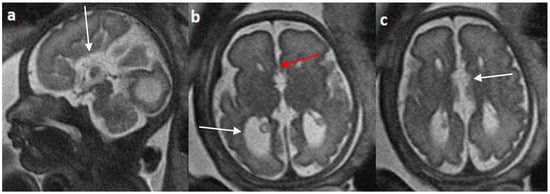

Associated CNS anomalies include 9/20 cases of interhemispheric cysts seen in 8 cases of complete agenesis and 1 case of hypoplasia. Out of 9 cases of IHC, 2 IHC were communicating with lateral ventricles. 4/20 (20%) cases had migration abnormalities such as gray matter heterotopia (Figure 8) in 3 cases of complete agenesis and hemimegalencephaly with schizencephaly in a case of dysplasia. 2 cases of cerebral cysts (2/20), including an arachnoid cyst in a case of complete agenesis class and a germinolytic cyst in a case of dysplasia. 3/20 cases of posterior fossa cysts, likely Blake’s pouch cysts, 2 in the complete agenesis class and 1 in the hypoplasia class. 2 cases of vermian hypoplasia (2/18) were noted, one each in the complete agenesis and hypoplasia classes (Figure 9 and Figure 10). A case of complete agenesis class had cerebellar hypoplasia and brain stem hypoplasia with a normal vermis. A case of complete agenesis class had a neural tube defect in the form of a sphenoidal meningoencephalocele. A case of dysplasia had diffuse thinning of white matter.

Figure 8.

Fetal MRI images of a 34 gestational weeks aged fetus, with complete agenesis of the corpus callosum and gray matter heterotopia. (a) A T2-weighted sequence image in mid sagittal plane showing complete absence of the corpus callosum with secondary changes in ventriculomegaly. (b) A T2-weighted axial sequence image showing associated subependymal heterotopia (white arrow) along the occipital horns of the bilateral lateral ventricles with moderate dilatation of lateral and third ventricles.

Figure 9.

Fetal MRI images of a 20 gestational weeks aged fetus with complete agenesis of the corpus callosum. (a) A T2-weighted sequence image in axial plane shows non-visualization of the corpus callosum, suggestive of complete agenesis. (b) A T2 weighted sequence axial image showing a well-defined extra axial fluid in the interhemispheric fissure. A lack of septum pellucidum was also observed. (c) The coronal plane shows an “steer horn” sign (arrow) in the anterior horn of the bilateral lateral ventricles and the absence of the corpus callosum and septum pellucidum in the midline region.